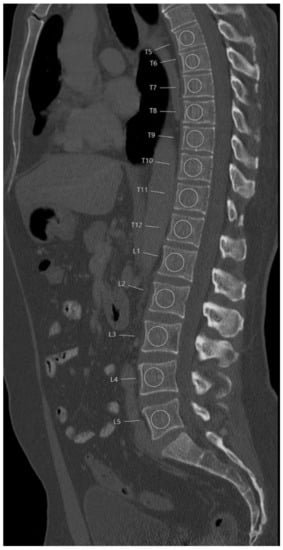

For BMD measurements in the baseline MDCT, circular regions of interest (ROIs) were defined and placed in vertebral bodies from Th5 to L5. Using the institutional PACS (Sectra AB; Linköping, Sweden) sagittal reformations of the spine with a slice thickness of 3 mm were selected for this purpose. In the most central slice depicting the vertebral body, ROIs were placed in the trabecular compartment of the anterior vertebral body excluding the cortical structures of the endplates. Additionally, inclusion of the vertebral venous plexus on BMD measurements was avoided. Each ROI diameter was standardized to two-thirds of the vertebral height (Figure 1). This approach has been reported previously [15,25]. BMD was not measured in vertebrae with prevalent fracture.

Figure 1. Representative placement of the regions of interest (ROIs). ROIs were placed in the ventral halves of the trabecular compartment of the vertebral bodies, equidistant to both endplates, excluding the venous plexus.